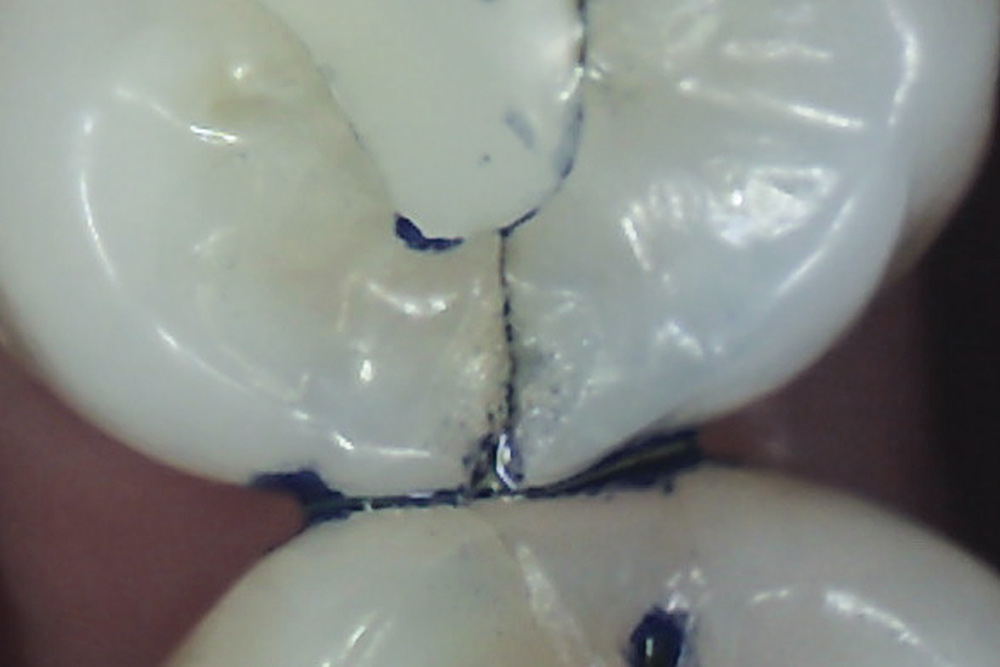

Methylene blue dye is the most commonly used dye to stain cracks because of its pooling tendency.2,3,14,16,17,23 The dye pools into the enamel and dentin cracks and the tooth is thoroughly rinsed. The resulting dark stain retained in the crack lines then helps enable cracks to be detected (Figure 4 and Figure 5). Methylene blue dye, however, also stains dental plaque, requiring the tooth surface to be cleaned with pumice or prophylaxis paste before dye application.14 The dye also can be absorbed by dentin, but any residual dye can be removed using a 10-second phosphoric acid etch.14 A comparative study of dye staining and transillumination concluded that methylene blue dye staining and transillumination performed simultaneously is the optimal crack assessment technique.23

Fig 4. Subtle asymptomatic occlusal crack (arrow) of a mandibular right second molar (occlusal view).

Figure 4

Fig 5. Methylene blue dye staining further revealing the occlusal extent of the crack shown in Fig 4.

Figure 5